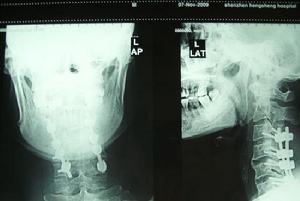

頸髓損傷X片臨床上通常可以通過X線顯示的頸椎骨折脫位的部位對頸髓損傷節段作出判斷,但有時頸椎的變化並不明顯,因此 需通過仔細檢查皮膚感覺障礙、肌肉運動障礙及反射的變化來確定。在解剖和功能的關係中,許多神經分布是交叉或重疊的,檢查時必須仔細加以辨認。有時甚至需經過反覆檢查,或從不同方向確定感覺障礙平面,才可獲得較準確的結論。頸3-4支配整個上頸部感覺,並表現為披肩狀分布的上胸部感覺。下位頸段損傷範圍需通過檢查上肢感覺分布來確定。

頸髓損傷的手術固定頸椎脊髓傷的治療目的包括:頸椎穩定性的重建和脊髓功能的恢復兩個部分。在很長一段時間內,以牽引外固定為 主的保守治療被廣泛套用於臨床,並被認為有較滿意的結果。然而,保守治療不可能使脊髓損傷有實質性改善,反而可能因重複微創傷阻礙神經功能恢復。此外保守治療固定不夠切實,即使是被認為最佳的頸部外固定裝置Halo背心也無法避免後期發生的頸椎畸形及頸後韌帶鬆弛。更為重要的是傷後長期臥床使併發症發生率增大,從而增加了死亡率。